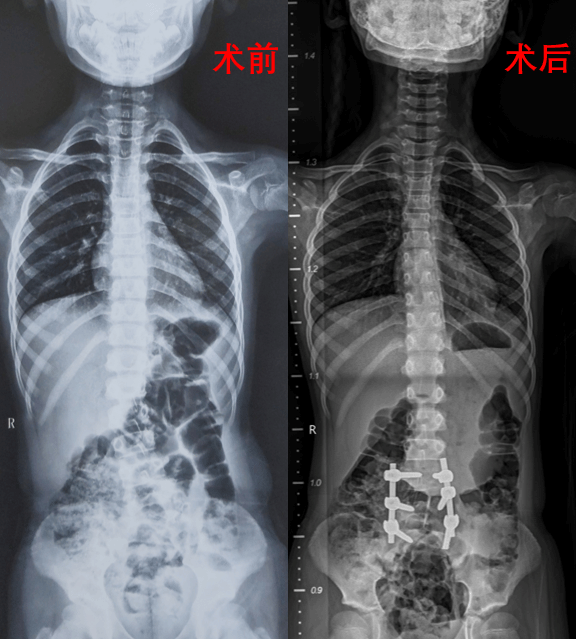

本次接受手术的两名患者均为7岁学龄期儿童,术前完善影像学检查提示分别为腰5和腰1半椎体畸形,脊柱侧凸Cobb角度分别达40°和58°,伴随明显躯干失衡。王栋主任团队通过脊柱全长X线、三维CT、MRI及神经电生理评估,为患者制定个体化3D打印模型及个性化手术方案,采用“后路脊柱侧凸截骨矫形+椎弓根螺钉固定+植骨融合术”,术中运用超声骨刀、术中神经监测等先进技术,在矫正畸形的同时最大限度保护脊髓功能。

手术过程由王栋主任主刀,分别在秦杰副主任医师、郭帅主治医师、郭秦规培医师以及张廷副主任医师、李京主治医师、刘亭规培医师的紧密配合下,由神经电生理监测团队、麻醉科全程护航,输血科保障血液供应。王栋主任表示:“青少年脊柱侧凸矫形是毫米级的精准手术,需在矫正畸形与保留脊柱生长潜能间取得平衡。"两例手术历时均控制在3小时内,出血量不足400ml,术后患者转入骨科加速康复(ERAS)病房,由护理团队实施精细化围术期管理和科室特色无陪护病房陪护团队的悉心呵护,两位患儿现均已在支具保护下下床活动。